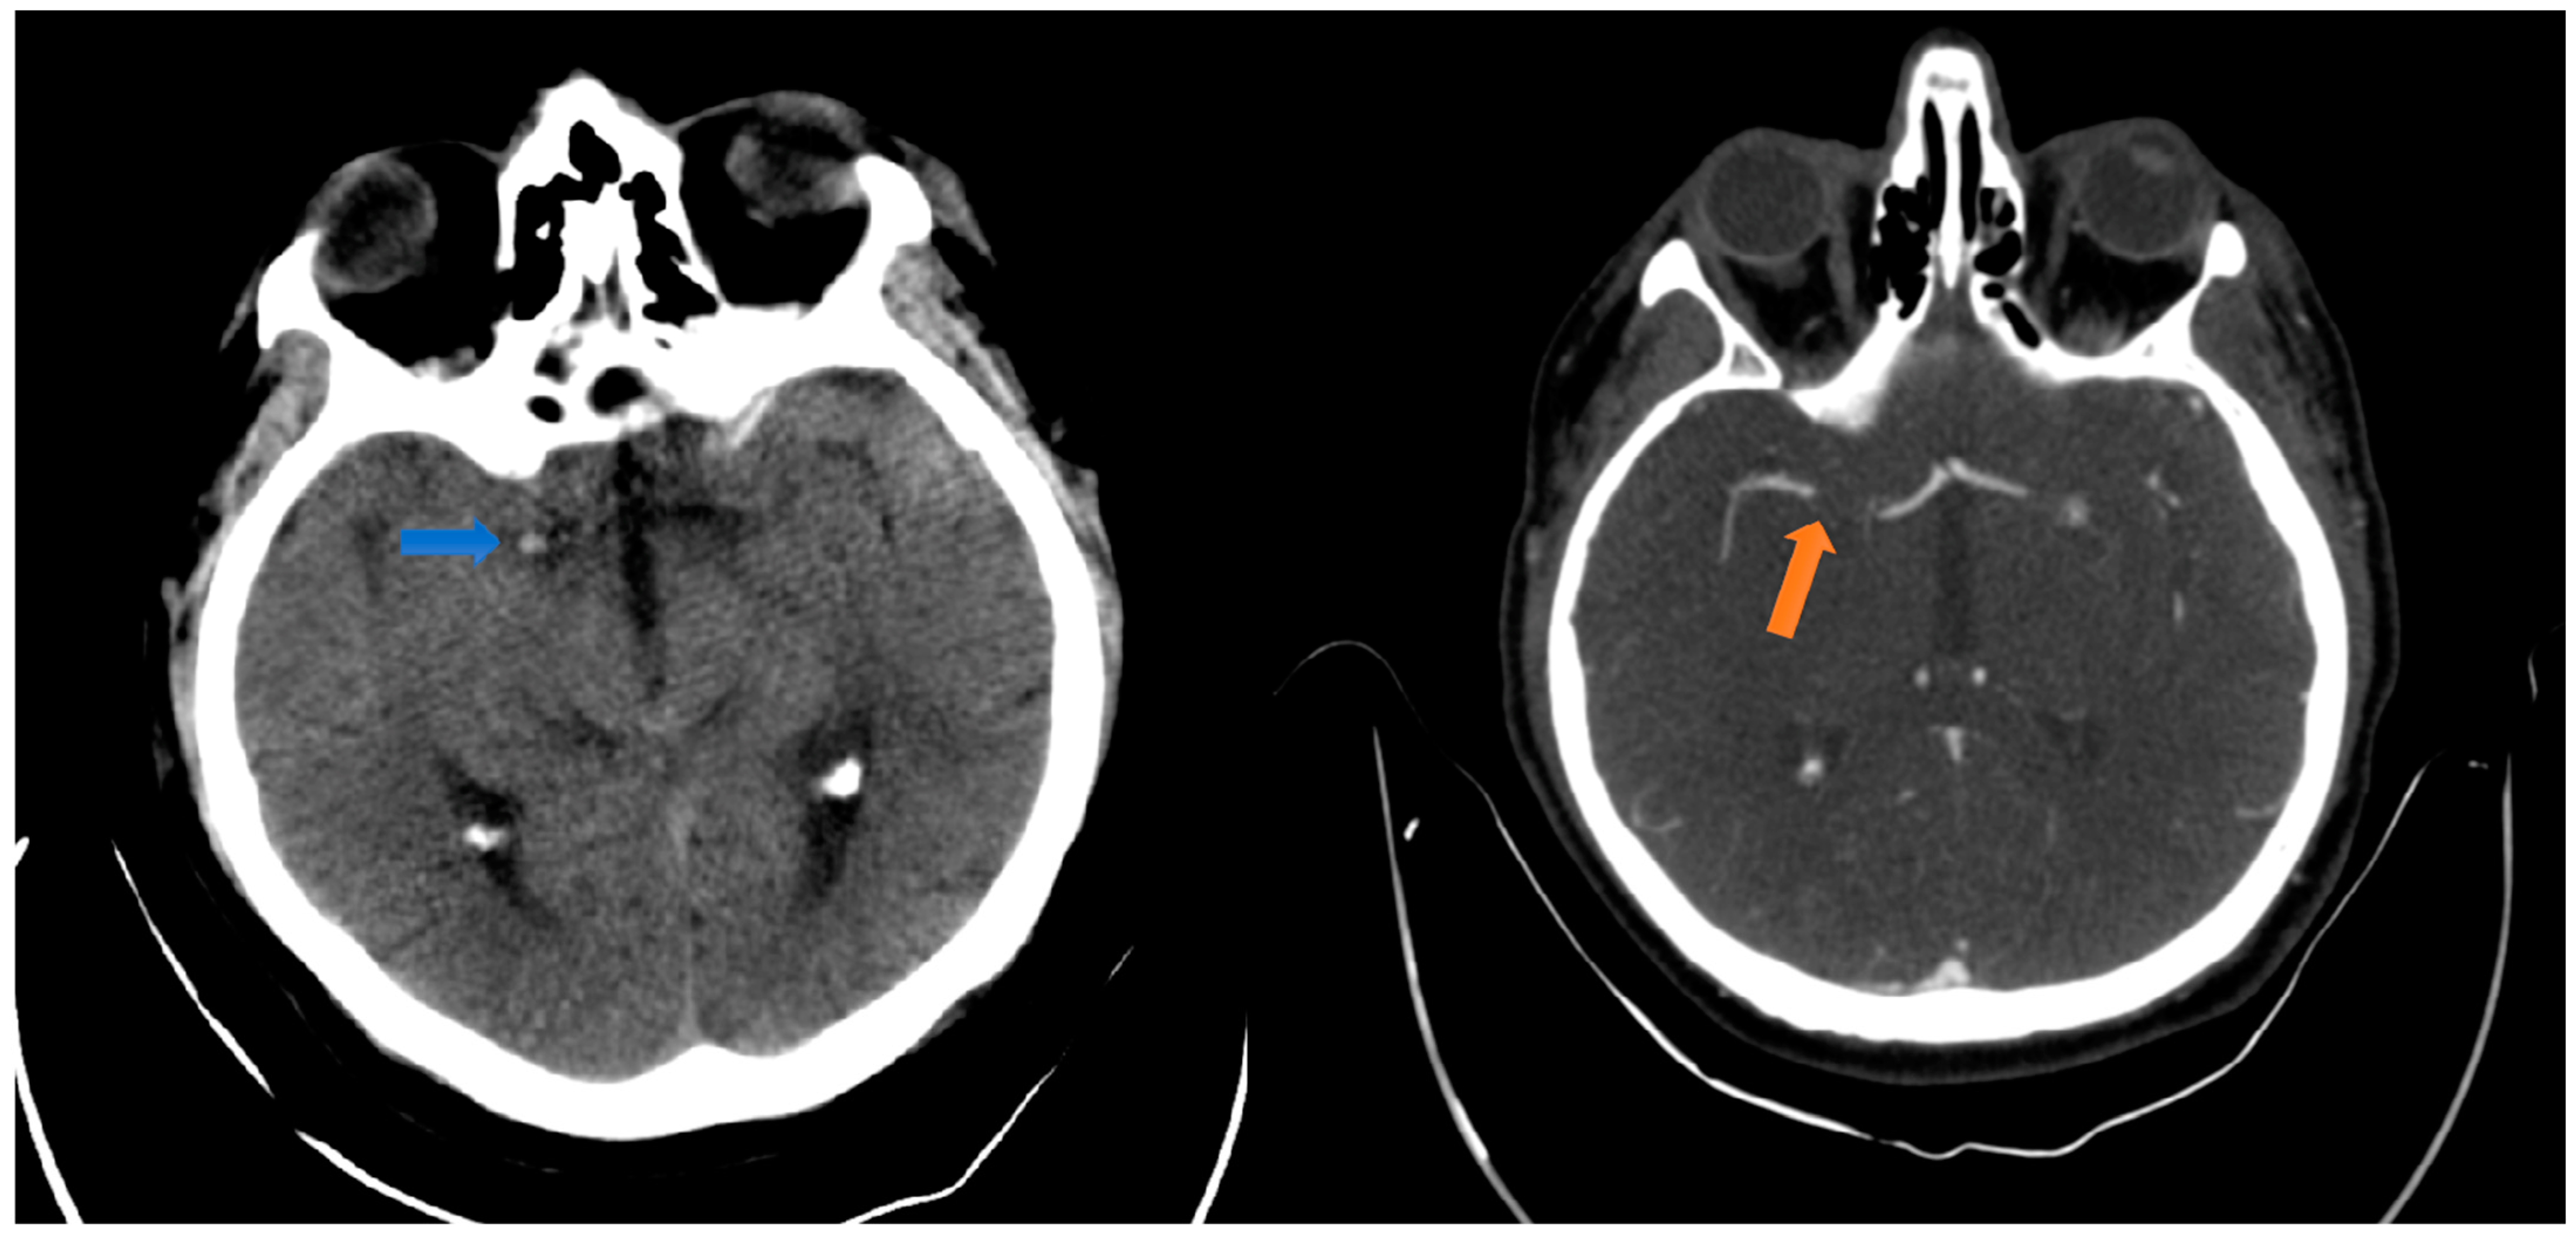

2.1. Case Presentation